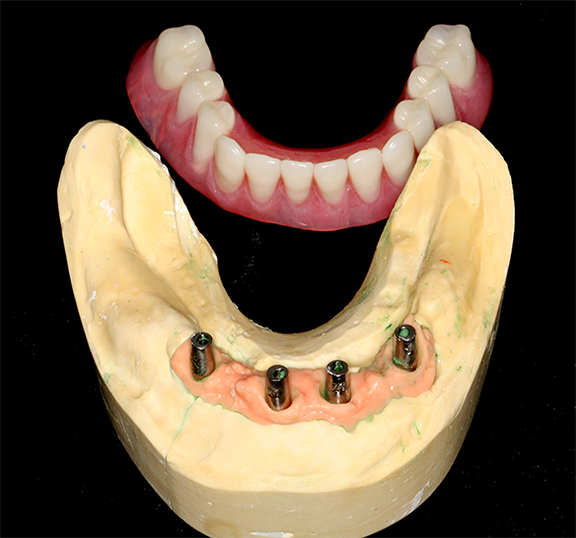

An implant-retained and implant-supported removable prosthesis may be fabricated by using a bar or a conical, titanium abutment with a 5-degree taper (Figure 18).49 In the next case, a fixture-level impression was made and records were registered and sent to the laboratory with the abutments (preselected based on the height of the mucosal cuff) for framework and prosthesis fabrication.49 The prosthesis had recesses on its intaglio surface to permit pickup of the abutment caps (Figure 19).49 The abutments were attached to the implants in the mouth (Figure 20). A jig/index provided by the laboratory (Figure 21) was used to seat the abutments intraorally so that they were positioned exactly as they were on the master cast. Gold caps were placed over the abutments and were picked up in the prosthesis intraorally (Figure 22).49 (Gold caps that fit over the abutments provide excellent retention, which improves over time.)50 The prosthesis was adjusted, finished, polished, and placed in the mouth (Figure 23). The prosthesis was entirely supported by the implant abutments.49 It had excellent retention and stability (almost like a fixed restoration) because it was entirely implant-supported; yet, it was removable.49

Fig 18. Conical abutments were used to retain an implant-supported removable prosthesis.

Figure 18

Fig 19. Recesses permitted pickup of the abutment caps.

Figure 19

Fig 20.  Abutments were attached to implants in the mouth (Atlantis Conus abutments, Dentsply Sirona).

Figure 20

Fig 21. A jig was provided to optimally position the abutments intraorally.

Figure 21

Fig 22. The abutment caps were picked up in the prosthesis.

Figure 22

Fig 23. The prosthesis was placed in the patient’s mouth.